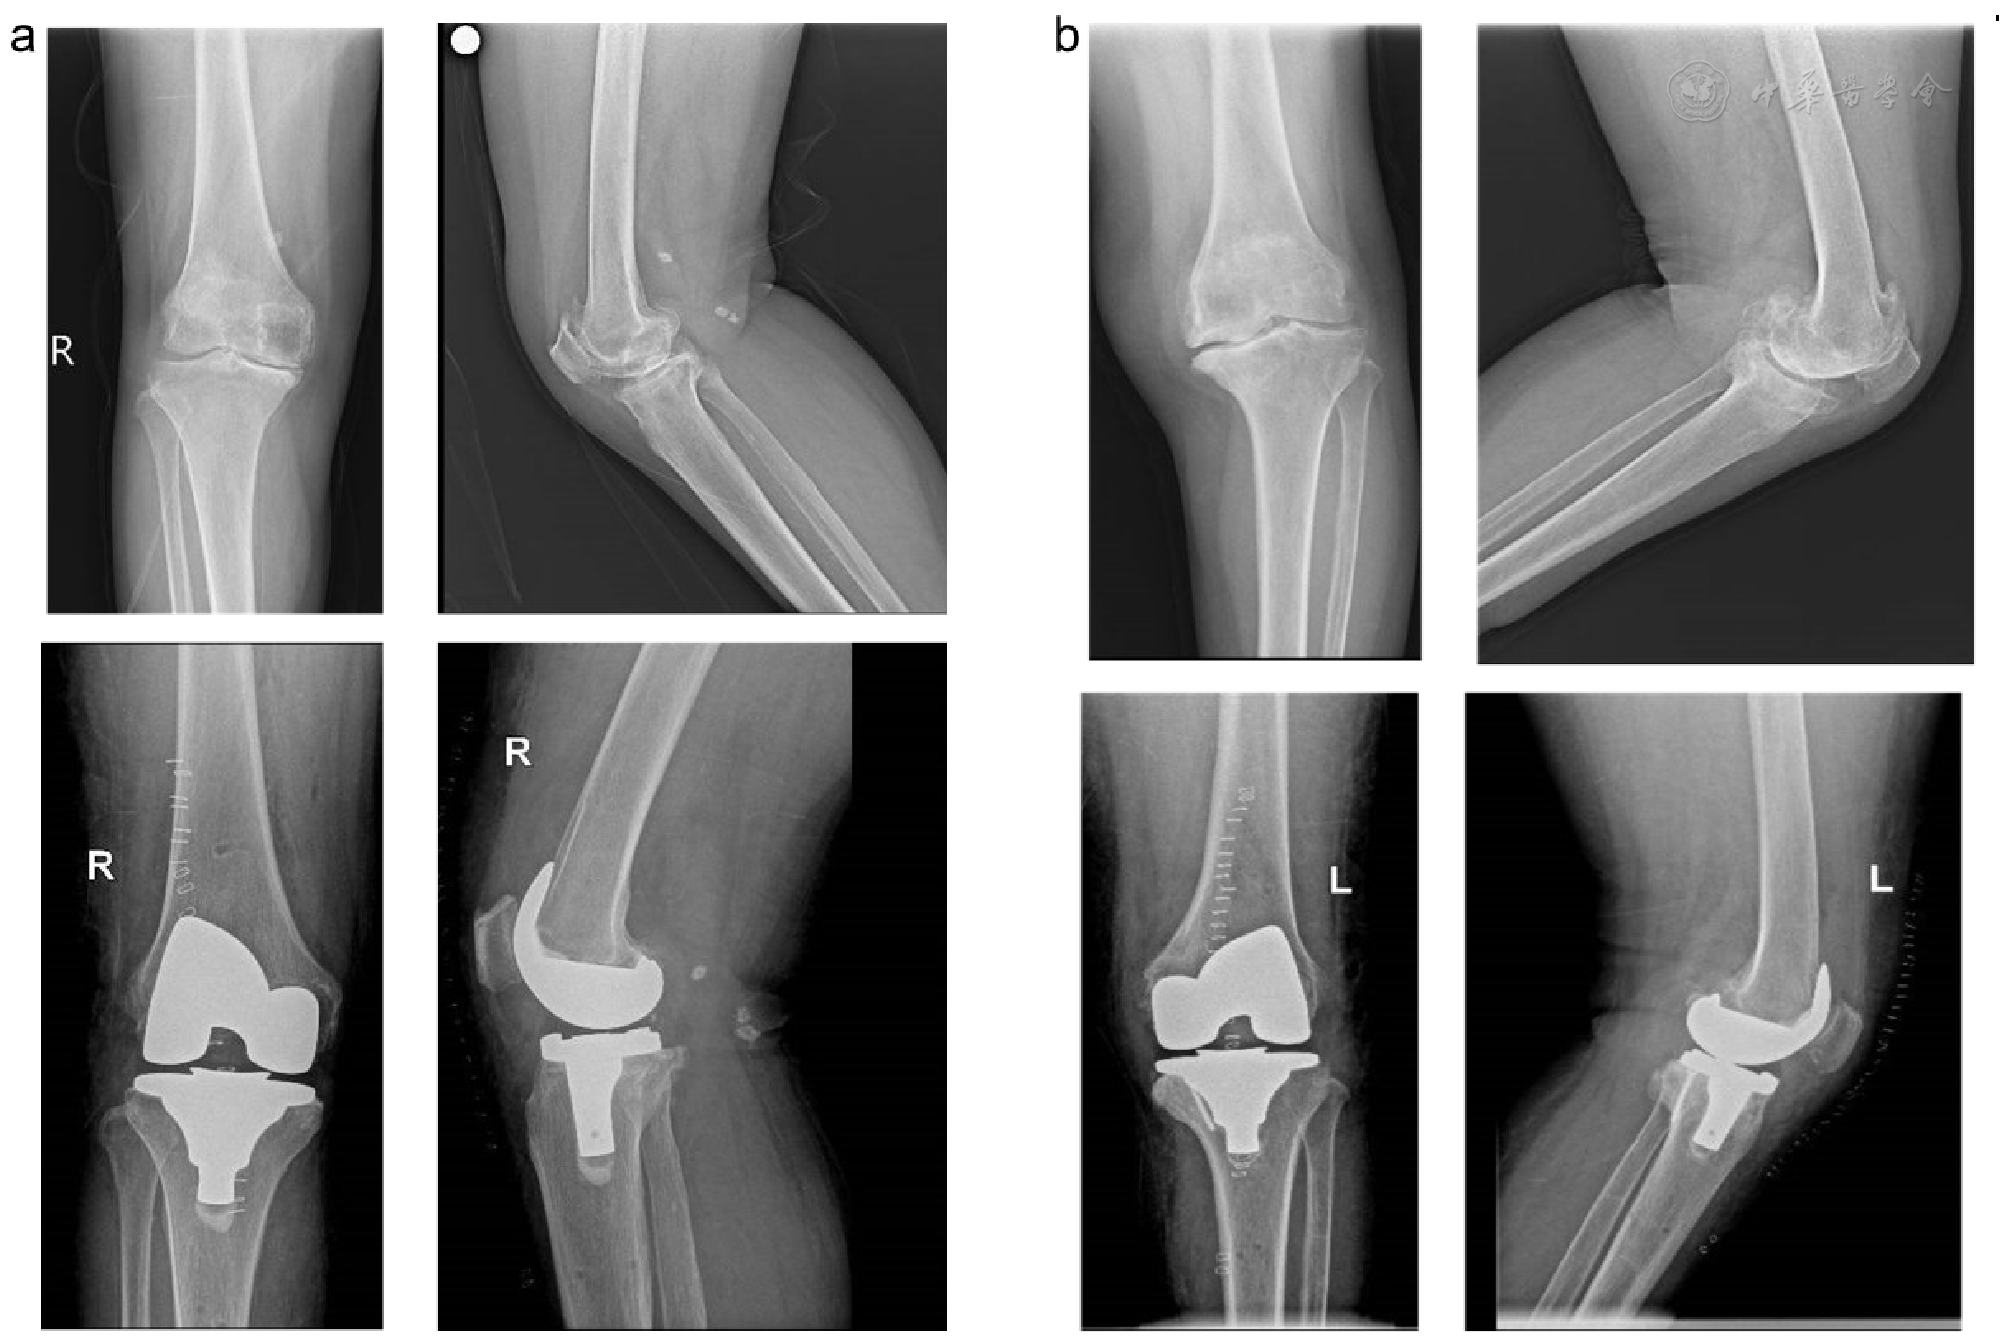

图1 两例典型患者影像学资料。图a 患者女,71岁,引流组,诊断:右膝关节骨性关节炎。图示膝关节置换术前术后膝关节正侧位。图b 患者女,70岁,非引流组,诊断:左膝关节骨性关节炎。图示膝关节置换术前术后膝关节正侧位。手术均由左建林教授主刀完成,术后假体角度精准